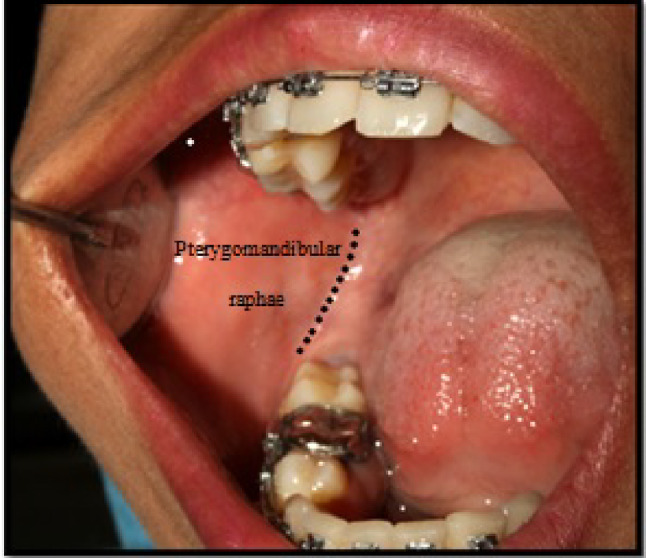

Informed consent was taken from the patients. All the patients were assigned randomly to one of the two groups. In the first session, the patients randomly received the CIANB or VA technique in one side of the oral cavity. One week later, the same patient received the other technique which was not received in the first session. In CIANB technique, the patient was positioned in semi-supine and asked to open the mouth wide to permit greater visibility of and access to the injection site. The injection site for this technique was the soft tissue covering the medial surface of the ramus at the lateral side of the pterygomandibular raphae and the external oblique ridge. The syringe was positioned between the premolars from the opposite site. Aspiration was carried out and 1.8 ml of local anesthesia with 2% lignocaine hydrochloride was injected slowly. Buccal nerve block was given at the mucous membrane distal and buccal to the most distal molar teeth in the arch (Figs. 1, 2 and 3).

Landmarks for classical inferior alveolar nerve block technique